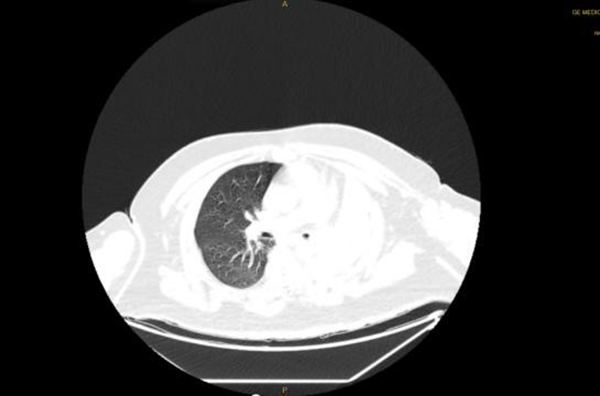

4月14日,王先生因“憋喘伴發(fā)熱咳嗽半月余”到徐州醫(yī)科大學附屬醫(yī)院急診就診。據(jù)王先生家人介紹,患者半個多月來,憋喘不斷加重,先后在徐州市多家醫(yī)院就診,考慮左肺不張伴感染,但通過積極抗感染治療,憋喘無改善并逐漸加重,同時出現(xiàn)發(fā)熱癥狀,體溫最高近39攝氏度。徐醫(yī)附院呼吸與危重癥醫(yī)學科何軍主任會診后,考慮患者智力異常,進食方式特殊,不排除誤吸的情況,閱片后發(fā)現(xiàn)左主支氣管內(nèi)存在異物可能,需行氣管鏡檢查進一步明確肺內(nèi)情況?紤]患者一般情況差,存在I型呼吸衰竭,肺部感染重等情況,于是將其收治在呼吸重癥監(jiān)護室(RICU)。

患者入院后進行高流量氧療和抗感染治療,因為其肥胖合并呼吸衰竭,肺部感染重,氣管鏡風險高,在與家屬充分溝通后,呼吸ICU團隊于4月15日為王先生行床旁氣管鏡檢查,鏡下發(fā)現(xiàn)左主支氣管內(nèi)一白色圓形異物,表面為壞死覆蓋,清除壞死組織后,異物質(zhì)硬,表面光滑,無法鉗取。同時患者病情危重、麻醉評估風險極高,在陳碧主任的主持下,呼吸ICU團隊經(jīng)過討論后決定行床旁氣管鏡取異物術。

季磊副主任醫(yī)師在楊翌、蔣宇及劉慧醫(yī)師的協(xié)助下,在全麻下經(jīng)氣管插管(8#)套管進鏡,左主支氣管內(nèi)可見被粘痰、壞死物包裹一圓形異物,清理后發(fā)現(xiàn)異物為花生粒,長徑約2cm,由于花生粒過大,無法通過8#氣管導管,于是將花生粒分解,通過使用圈套器、異物鉗以及網(wǎng)籃逐一將其取出,總共歷時1.5個小時。取出異物后,左主支氣管及其分支可見大量黃色膿性分泌物,予以充分吸除。

后續(xù)給與積極抗感染等治療,復查胸片示左肺不張改善,體溫正常,炎癥指標下降,再次復查氣管鏡下可見痰量較前明顯減少,總體病情好轉,4月23日轉到普通病房繼續(xù)治療;颊呒覍俦硎,輾轉三家醫(yī)院就醫(yī),還是徐醫(yī)附院最值得信任,對呼吸ICU全體醫(yī)護人員表達了敬意和衷心感謝。